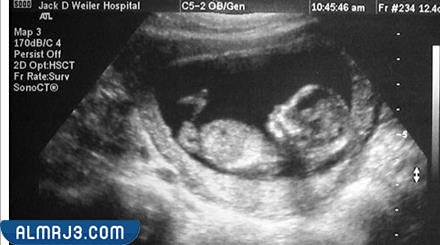

شكل الجنين البنت في السونار، يختلف شكل كلًا من الجنين الأنثى والجنين الذكر في السونار بشكل واضح جدًا، وذلك أثناء شهور الحمل المختلفة، خاصة وأن أجهزة السونار من التقنيات الطبية المميزة التي توضح شكل الجنين البنت بسهولة وذلك من خلال ملاحظة الأعضاء التناسلية الخاصة بها والتي تختلف في الجنين البنت عن الولد، في سياق الحديث عن الجنين البنت يهتم موقع المرجع بتسليط الضوء على شكل الجنين البنت في السونار بالتفصيل.

يكون شكل الجنين واضح ومميز في أجهزة السونار بداية من الشهر الرابع من الحمل، ولكنه ويزداد وضوحًا كلما اقتراب موعد الولادة، وبشكل عام يمكن تحديد شكل الجنين البنت من خلال فحص الأعضاء التناسلية الخاصة، إذ تملك الجنين البنت شفرتين، وذلك بالإضافة إلى العضو التناسلي، والذي يستطيع طبيب النساء المتخصص من تحديده بمنتهى السهولة، فتتشابه الأعضاء التناسلية الخاصة بالجنين البنت إلى حد كبير مع شكل الهمبورجر.[1]

وفي الشهر الرابع من الحمل يمر الجنين بالعديد من التغيرات، والتي يستطيع الطبيب ملاحظتها داخل أجهزة السونار بمنتهى السهولة، وذلك مع تكون كل من الجلد والأعضاء التناسلية، فستكون لدى الجنين البنت شفرتان، وذلك إلى جانب العضو التناسلي الخاص بها، والذي يمكن رؤيته بسهولة في حال كانت تأخذ الجنين البنت وضعية مناسبة لذلك الأمر.

يمكن التعرف على نوع الجنين البنت بداية من الشهر الرابع من الحمل خاصة في حال كانت تأخذ وضعية مناسبة داخل الرحم؛ ومن ثم يمكن رؤيتها بسهولة باستخدام أجهزة السونار، وعلى الرغم من ذلك، إلا أن هناك الكثير من الأطباء التي تنصح بأهمية التعرف على نوع الجنين في الشهر الخامس حتى تتأكد الأم من نوع الجنين البنت، وذلك لأن أجهزة السونار قد تخطئ في بعض الأوقات خاصة، إذ تم الاعتماد عليها في وقت مبكر للتعرف على نوع الجنين.